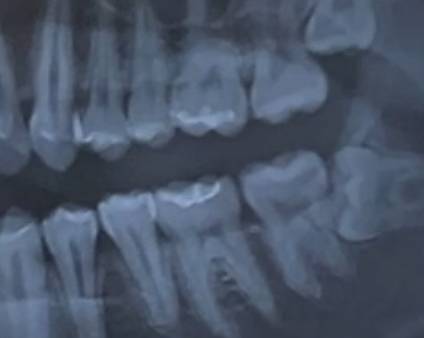

이거 지금 치아 엑스레이 사진인데

위아래 뒤에서 두번째 어금니 둘다

하얀 부분이 예전에 충치치료 했던곳인가?

사랑니많다

ㅇㅇ충치치료했던부분같음

웅 충치치료한 거

근데 사랑니 뽑아야겠다

그렇지만 n7번 치아에 문제 생겨서 임플란트 하는 것보다 나을지 몰랑

2030대 환자분들 임플란트 하는 이유가 사랑니때문인 거 꽤 많앙

22 아래 저거는 아예 누웠넹 얼렁 빼는게 좋아ㅠ

사랑니 빨리 뽑으십셔… 누운애는 빨리 처리할수록 뒤탈이 적다ㅠㅠ